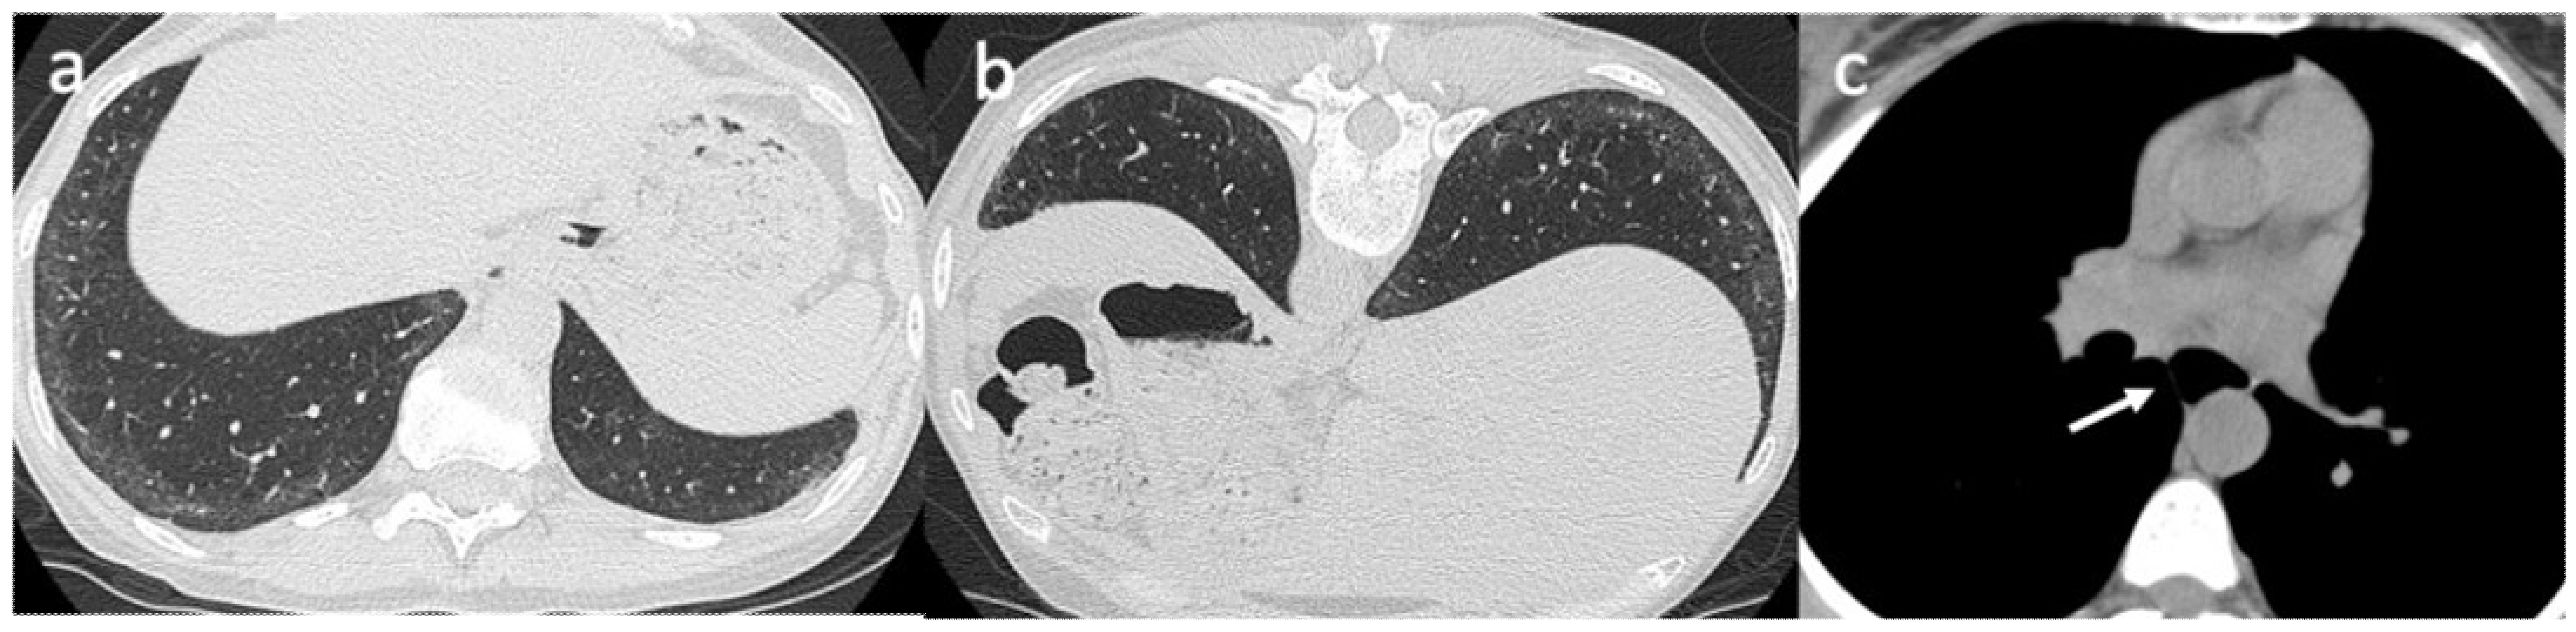

4. Imaging